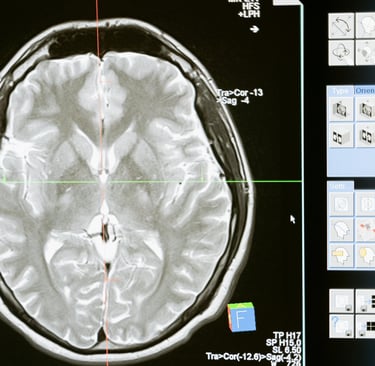

מחקרים בתחום הנוירו-פסיכולוגיה מראים בבירור: המוח שלנו לא תמיד מבדיל בין חוויה ממשית לבין חוויה מדומיינת

מחקרים בתחום הנוירו-פסיכולוגיה מראים בבירור:

המוח שלנו לא תמיד מבדיל בין חוויה ממשית לבין חוויה מדומיינת.

בזמן שאנחנו מדמיינים משהו באופן מוחשי, מופעלות במוח אותן מערכות עצביות שפועלות כאשר אנחנו חווים את הדבר במציאות.